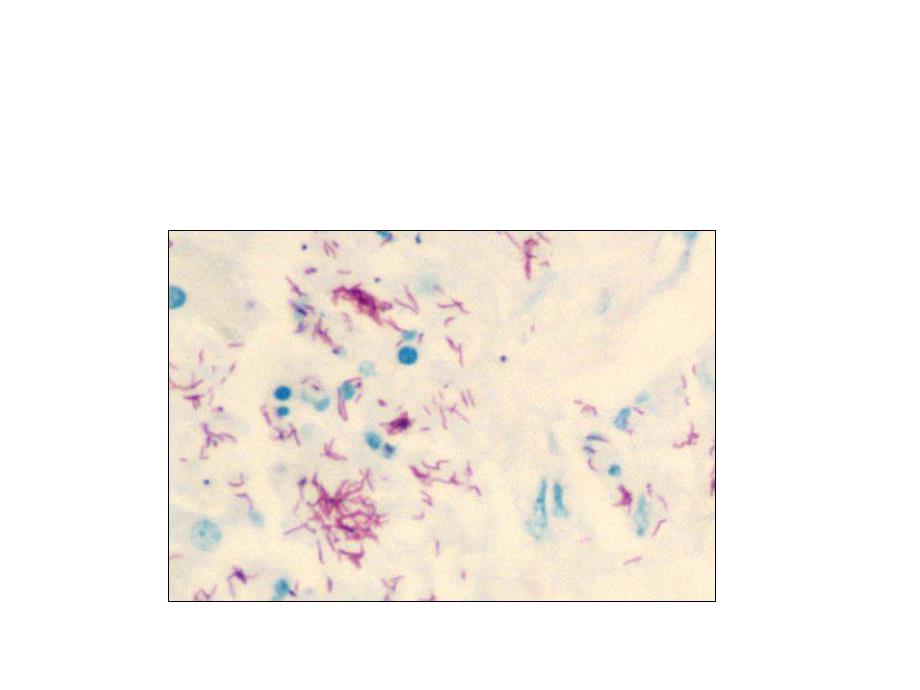

2、第一节第一节 结核分枝杆菌结核分枝杆菌生物学特性生物学特性形态染色:形态染色:菌体细长微弯,菌体细长微弯,有分枝,排列不规则,多单有分枝,排列不规则,多单个散在,易发生个散在,易发生L型,抗酸染型,抗酸染色阳性色阳性 结核分枝杆菌(结核杆菌)为结核病的病原体结核分枝杆菌(结核杆菌)为结核病的病原体n培养特性培养特性专性需氧,温度专性需氧,温度37,pH偏酸偏酸6.5-6.8营养要求高,罗氏培养基营养要求高,罗氏培养基(蛋黄、甘油、天门冬素、(蛋黄、甘油、天门冬素、马铃薯、无机盐、孔雀绿马铃薯、无机盐、孔雀绿等)等)生长缓慢,生长缓慢,18h分裂一次,分裂一次,2-4W形成形成R型菌落,型菌落,

9、染初期,老年人,严重结核合并其它传染病病使用免疫抑制剂使用免疫抑制剂艾滋病等免疫功能低下者艾滋病等免疫功能低下者微生物检查与防治微生物检查与防治n 微生物学检查微生物学检查 1 直接涂片染色观察,菌数少时需浓缩集菌直接涂片染色观察,菌数少时需浓缩集菌 2 分离培养鉴定及快速诊断分离培养鉴定及快速诊断n 防治防治 1 应用卡介苗预防接种应用卡介苗预防接种 2 治疗原则:早期、大量、长期、联合用药治疗原则:早期、大量、长期、联合用药 第三节第三节 麻风分枝杆菌麻风分枝杆菌 一、一、生物学特点生物学特点 其大小、形态、染色均与结核杆菌类似,其大小、形态、染色均与结核杆菌类似,但菌体略粗,多存在于细胞